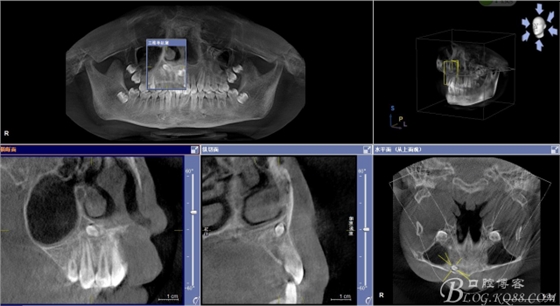

圖3.cbct影像檢查:12與13根尖上方也有一顆倒置多生牙,接近鼻底。

圖4.三維重建影像:12根尖區(qū)的多生牙位置更高。手術(shù)難度大